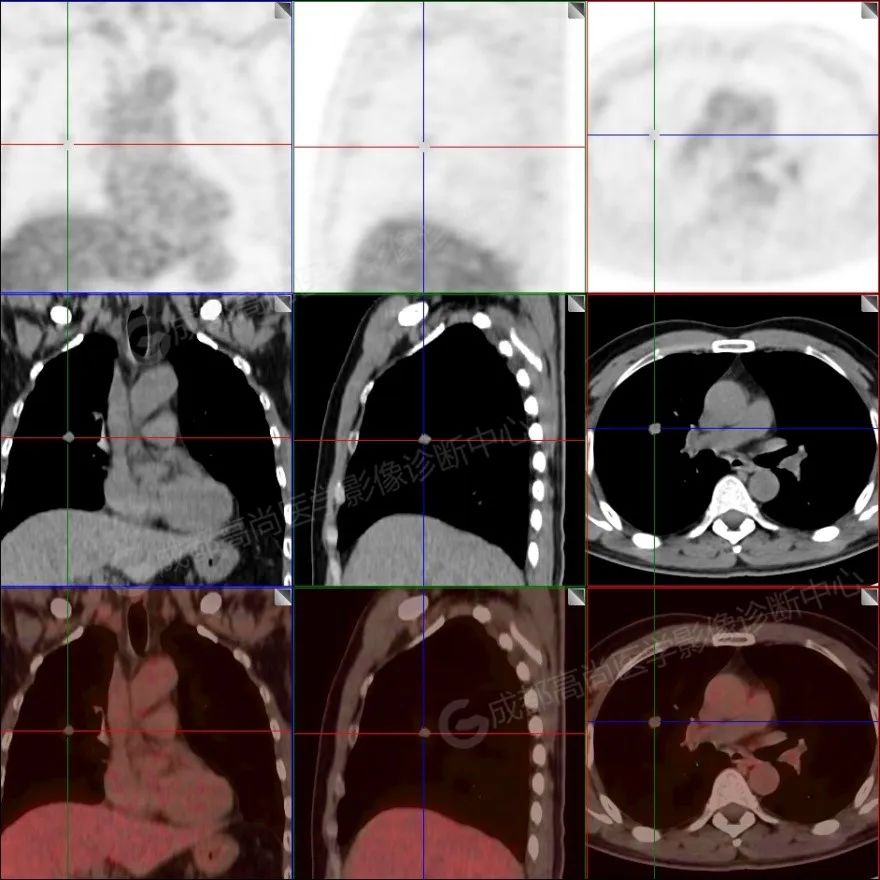

【PET/CT 融合图】

PET/CT 检查示:

右肺上叶前段及右肺中叶外侧段分叶状软组织结节,该病变骑跨水平裂胸膜,大小约 1.5 cm×1.3 cm×1.6 cm(上下径),边界清晰,其内密度欠均匀,CT 值约 18 Hu,FDG 摄取未见明显增高。

PET/CT 诊断:1. 右肺上叶前段及右肺中叶外侧段见一分叶状软组织结节影(约 1.5 cm×1.3 cm×1.6 cm),该病变骑跨水平裂胸膜,FDG 摄取未见明显增高,考虑为良性肿瘤,请结合病理协诊。

七、病例小结及讨论

该病例为患者体检发现右肺结节,PET/CT 见该结节光滑,位于叶间胸膜处,但胸膜无明显牵拉受侵,FDG 摄取未见明显增高,若以实性为主的肺癌大部分 FDG 摄取为较明显增高,位于胸膜处亦会出现毛刺及胸膜牵拉凹陷等征象,该病例不具备恶性肿瘤征象,PET/CT 可以很好的鉴别;肉芽肿性炎常会有不同程度 FDG 摄取,边缘不光滑,形态常不规则,多病灶;结核球常有卫星灶,中央干酪样坏死多见,多无 FDG 摄取;硬化性肺泡细胞瘤  女性多见,体积多比肺错构瘤大,周围可见晕征,增强后可见血管贴边征等,FDG 摄取不同程度增高。上述鉴别 PET/CT 具体独特优势,当然「同病异影、异病同影」,影像千变万化,除了要有扎实的影像基本功,还要结合临床综合分析,且不能代替病理。